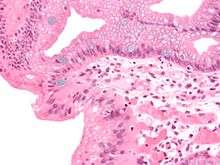

| Micrograph of a gastro-esophageal junction with pancreatic acinar metaplasia. The esophageal mucosa (stratified squamous epithelium) is seen on the right. The gastric mucosa (simple columnar epithelium) is seen on the left. The metaplastic epithelium is at the junction (center of image) and has an intensely eosinophilic (bright pink) cytoplasm. H&E stain. | |